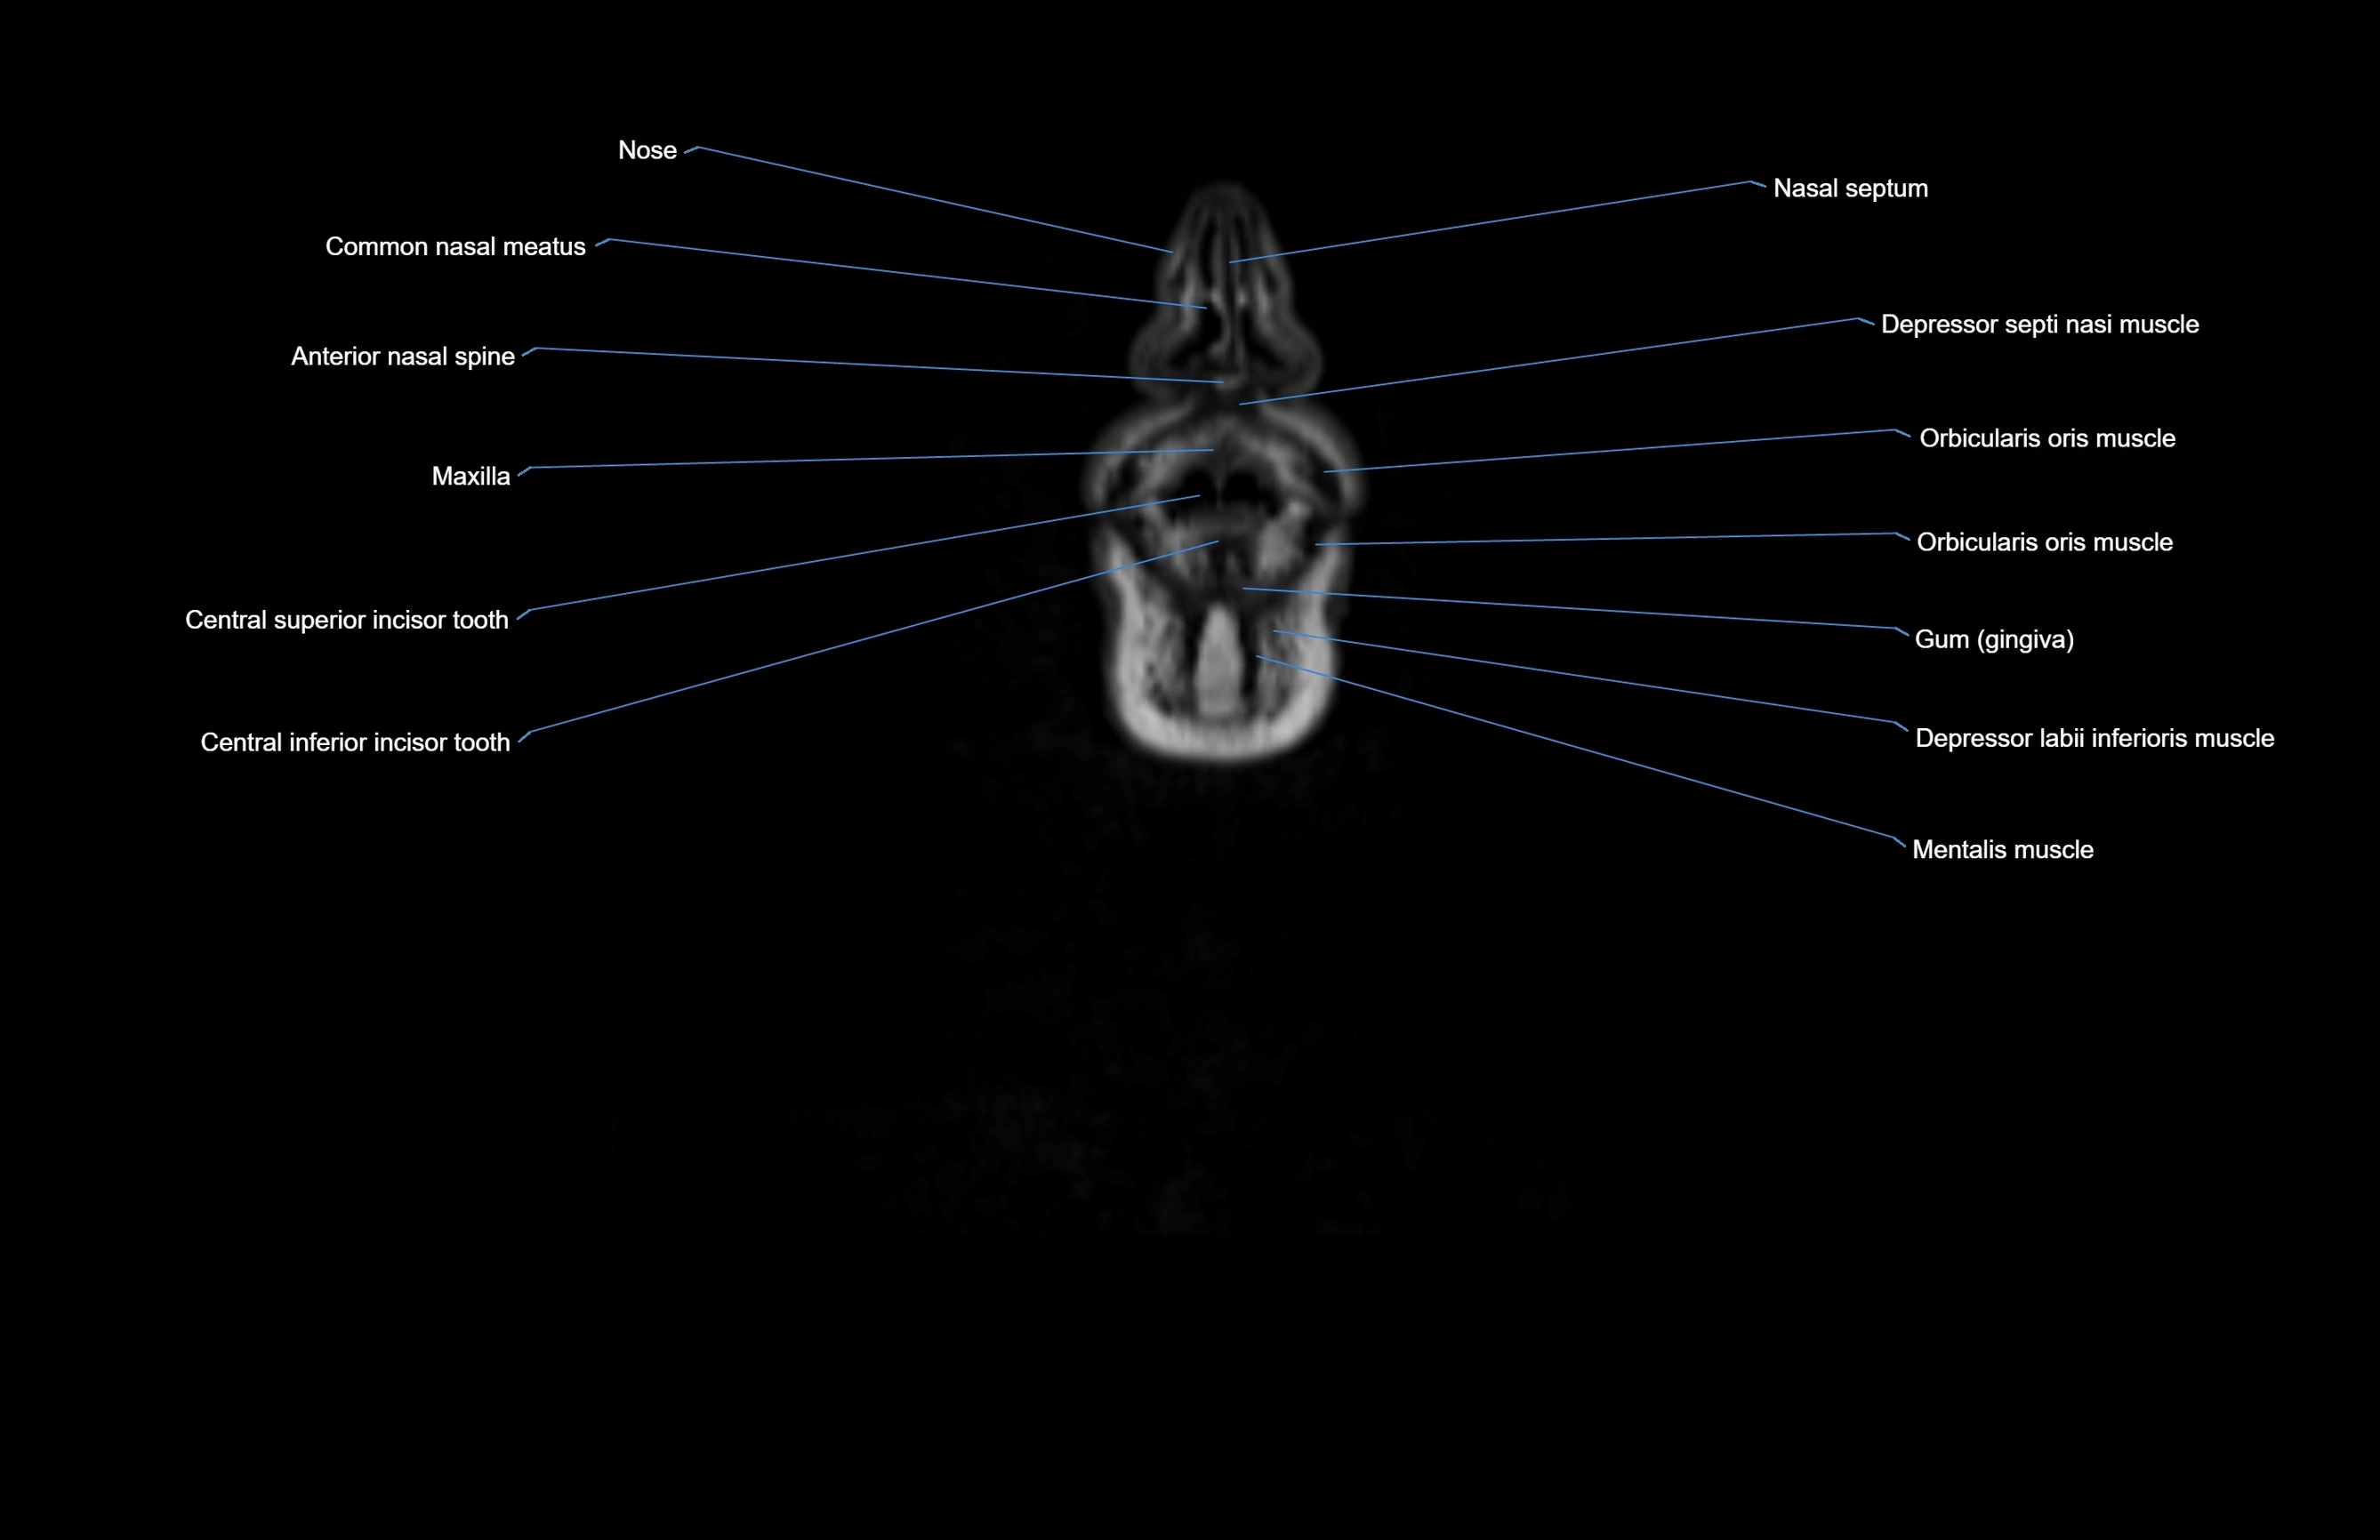

MRI images